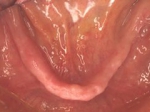

術前(下顎粘膜面、鏡像)